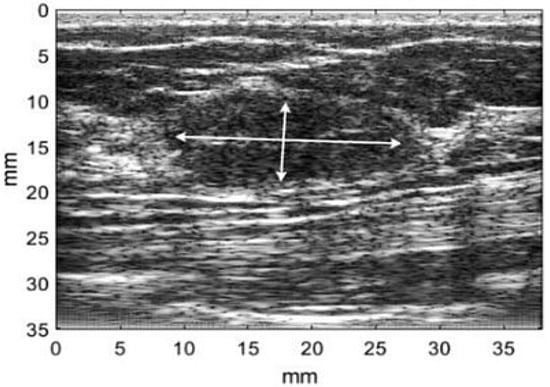

- Gomez, W.; Leija, L.; Alvarenga, A.V.; Infantosi, A.F.C.; Pereira, W.C.A. Computerized lesion segmentation of breast ultrasound based on marker-controlled watershed transformation. Med. Phys. 2010, 37, 82–95. [Google Scholar] [PubMed]